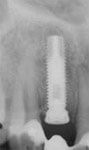

Das Röntgenbild mit dem Implantat und der provisorischen Klebebrücke.